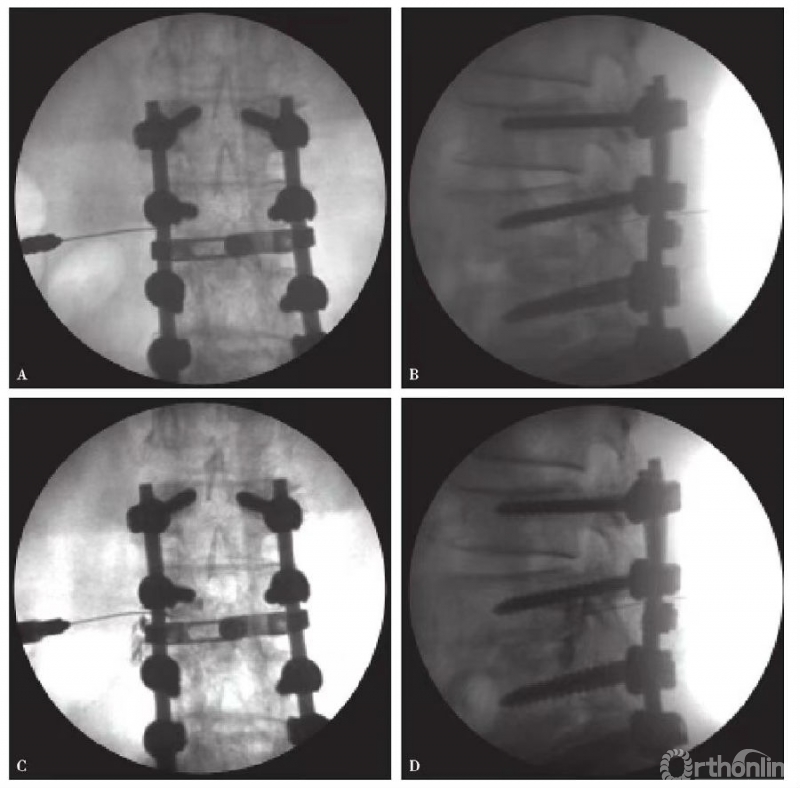

4.选择性神经根造影及阻滞术结果判断未阻滞:不是责任受累神经根;部分阻滞:部分责任受累神经根,仍存在其他受累神经根可能;完全阻滞:明确责任受累神经根(图2、图3)。

图2 选择性腰5神经根造影 A、B.穿刺成功正侧位片;C、D.造影后正侧位片

图3 选择性L3神经根造影 A、B.穿刺成功正侧位片;C、D.造影后正侧位片